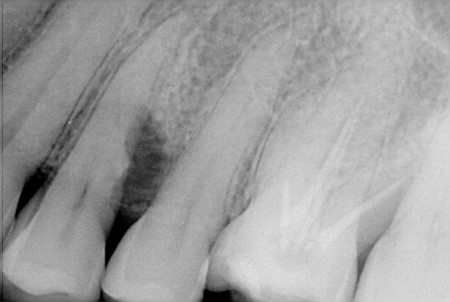

歯周病治療では検査がとても重要です。

レントゲンで歯を支えている骨(歯槽骨)の状態を調べます。

主に、今現在「口の中のどの場所でどれぐらい歯周病が進行しているか」を診断します。